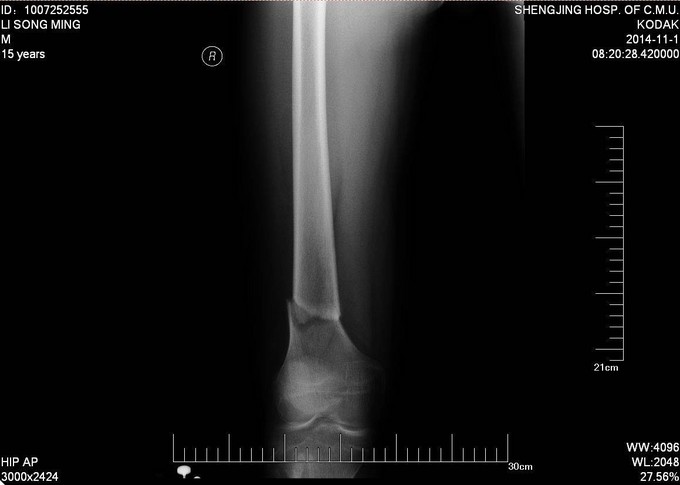

患者及家属自述于2014年10月31日,在学校与同学打闹过程中不慎别伤,伤后自觉右大腿疼痛伴有活动受限,就诊于当地医院行股骨正侧位X线片提示:右股骨远端骨折。未于治疗。后患者为求进一步诊治来我院急诊就诊,请我科会诊后,诊断为右股骨远端骨折,建议手术治疗,收入病房。伤来饮食、睡眠欠佳。大小便正常,体重无明显变化。

专科查体:见右大腿肿胀,畸形。大腿远端压痛阳性,轴向叩击痛阳性,可触及骨擦音,骨擦感。见双足高弓扬趾,右侧足背伸肌力5级,足背动脉可触及。

诊断:右股骨远端骨折 患者入院后急诊行生化检查等,查无手术禁忌症后急诊行右胫骨结节骨骼牵引术,维持患肢长度,减轻患者疼痛后,完善相关检查,请相关科室会诊后,查无明显手术禁忌症后行右股骨远端骨折闭合复位Liss钢板内固定术。